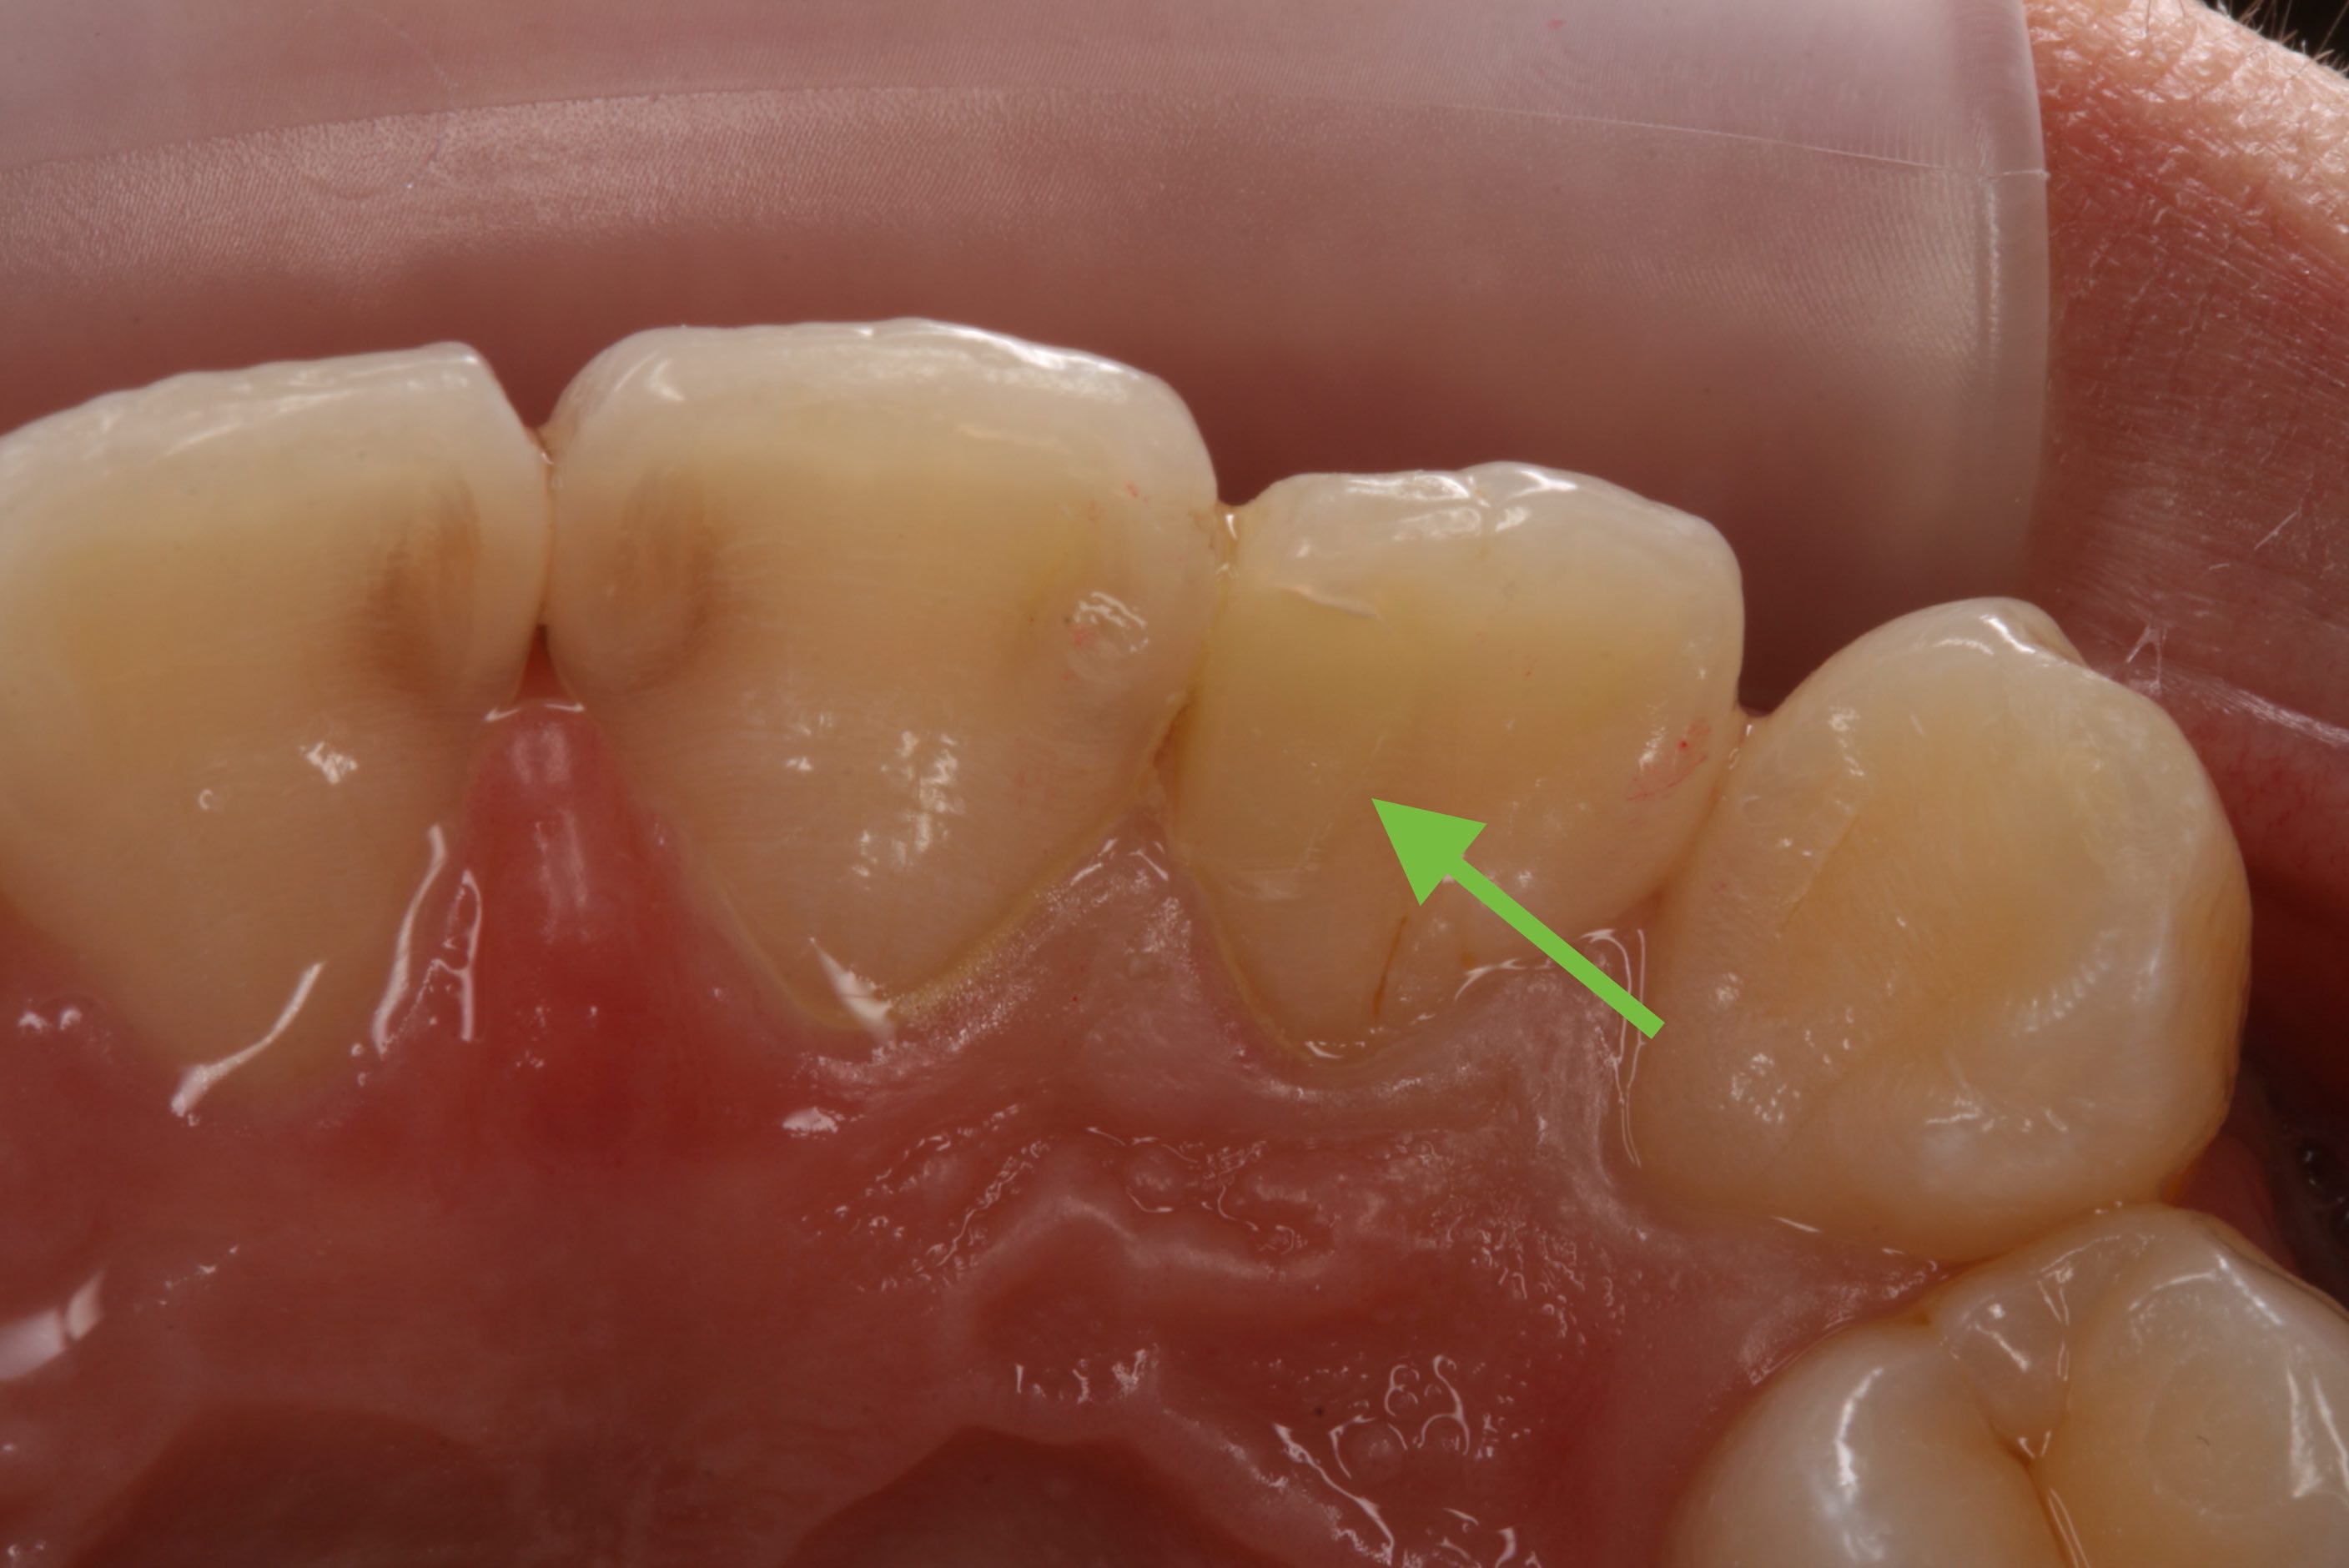

ティーンエイジャーの歯はまだ完全に成熟していないので、虫歯の穴は小さく見えても深く大きく広がりやすく、中の神経にまで進んでいることがあります。

そこで、意図的に虫歯を少し残して、間接的に神経を温存する薬を塗り、とりあえず歯に詰め物をして終了します。その後、定期的にレントゲンを撮影して、象牙質ができたか確認し、もう一度残してきた虫歯を取り除いて詰め物をします。薬は抗生物質(3MIX)よりもHYカルボテンポラリーソフトの方が学会のお墨付きもあり、予後が良いです。